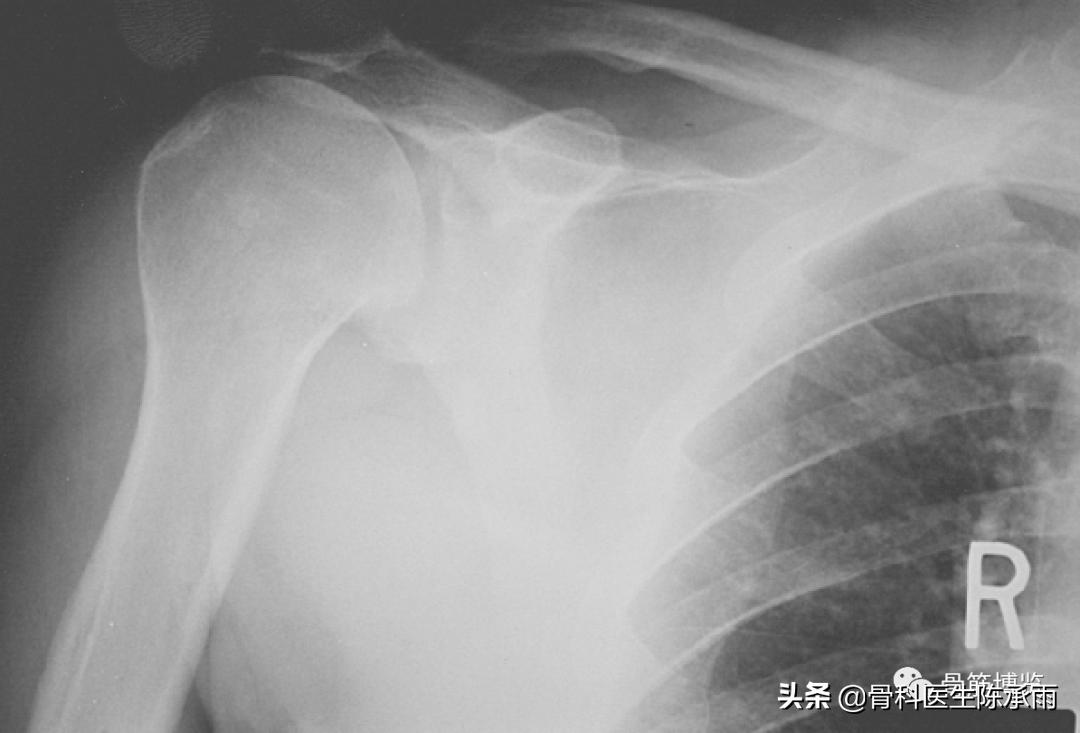

巨大肩袖损伤肩峰下间隙<9mm